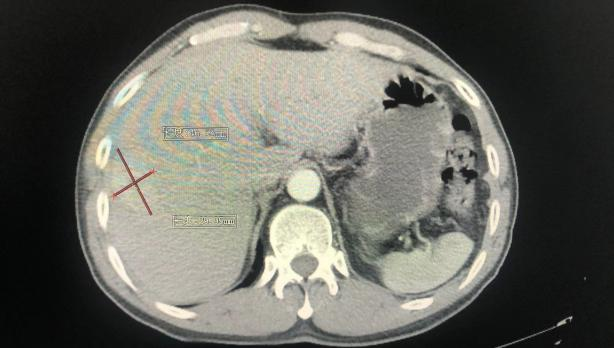

患者为53岁男性,因“右上腹部疼痛不适3月,加重半月”来我院就诊,入院后查腹部增强CT及普美显造影增强MR检查提示肝S8占位,考虑肝细胞癌可能。同时患者肝细胞癌特异性肿瘤标志物甲胎蛋白明显升高并且有乙型肝炎病毒感染背景。通过检测吲哚菁绿(ICG)代谢率评估患者肝脏肝细胞储备功能以及测算残余肝脏体积,同时排除其他手术禁忌症,肝胆胰外科学科带头人古松钢副主任医师决定为患者实施精准解剖性肝段切除术—荧光腹腔镜下解剖性肝S8背侧段切除术。